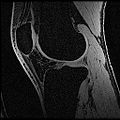

The aim of this project is to develop a methodology for rapid segmentation of knee structures from magnetic resonance (MR) images for subject-specific modeling. The overall goal can be broken down into two specific objectives -

Objective 1: We have adopted a multi-contrast MR methodology to segment knee bones and cartilage structures. The algorithm utilizes tissue intensity information from multiple MR contrasts to segment structures of interest. Inputs to the algorithm included n registered MR image sets. The algorithm created an n-dimensional space of voxel intensities associated with the n image sets. The user assigned seed points to the structures of interest, and the algorithm created a cluster center for each structure of interest. Cluster radii were calculated based on standard deviations obtained from seed points, and tissue structures were classified as label maps.

• Generated label maps of knee and hip structures.